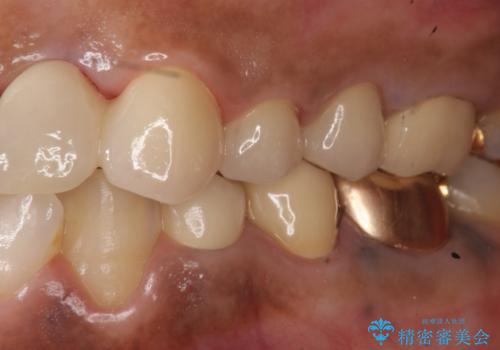

- 左上2番目の歯がグラグラするので診て欲しいといらっしゃった方の症例です。

左上2番目の歯は歯根が破折してため抜歯し、左上123のブリッジによる欠損補綴を行いました。

左上4、5番目の歯は根尖病変を認めたため再根管治療を行い、オールセラミッククラウンによる補綴を行いました。

なお左上4に関しては縁下歯質を改善するため、歯冠挺出を行っております。